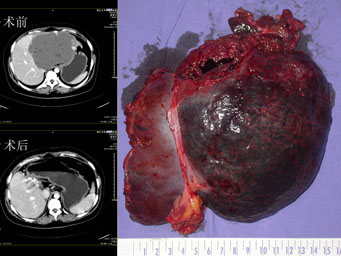

课题组针对目前腹腔镜肝胆胰脾存在的难度和热点,进行系统的临床研究,解决了这些领域存在的难题,为临床应用和推广奠定基础。在肝脏外科方面,提出腹腔镜下区域性肝脏血流阻断技术;改制了一种腹腔镜肝切除使用的多功能手术解剖器,解决了腹腔镜肝切除术中出血和气体栓塞的两大世界性难题,提高了手术成功率(85.7%→96.8%),减少了并发症(23.8%→3.2%)。完成了255例完全腹腔镜肝切除术, 其中左半肝切除41例,右半肝切除2例,尾状叶切除3例;首创经脐单孔法肝囊肿开窗引流术;在胆道外科方面,创建冲吸钝性解剖法显露肝总管、胆囊管及胆总管“三管”解剖关系及国内率先开展腹腔镜胆囊切除术中胆道造影技术,解决了胆道损伤和术后胆总管结石残留两大难题;在脾脏外科方面,创造性提出腹腔镜二级脾蒂离断法脾切除术,解决了依赖进口手术器械和胰漏两大问题;在胰腺外科方面,完成国内首例完全腹腔镜下胰十二指肠切除术。项目成果推广应用医院165家,培养国内外进修医生1000余人,病人来自全国各地及美、英、法等国,举办国家级医学继续教育学习班8期,共培训学员500余人,技术辐射26个省、市、自治区。